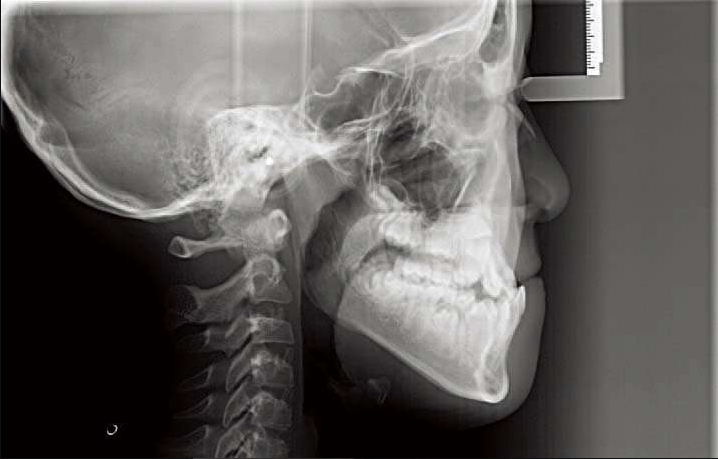

1)首先看下颌骨形态

如果是高角,情况不妙,这种反𬌗难做,而且效果不好,容易复发;如果是均角或者低角,矫治效果不错而且稳定不容易复发。

如果是上颌后缩,这种反𬌗也相对好做一些。但是如果是下颌前突,这种情况很悲哀(下颌骨可能会随着生长越来越前突,反𬌗可能会加重)。

如何鉴别上颌后缩?还是下颌前突?

头影测量中有一个方法简单有效:

从N点(鼻根点)做眶耳平面的垂线,即Mcnamara线,上颌骨A点(上齿槽座点)距离该垂线的正常距离:0mm(儿童),1~2mm(成人);

下颌骨Pog点(颏前点)距离该垂线的正常距离:−6mm(儿童),−2mm(成人)。

图11 鉴别上下颌位置

①Pog点到Mcnamara线的距离;②A点到Mcnamara线的距离。

图12 上颌后缩

图13 下颌前突